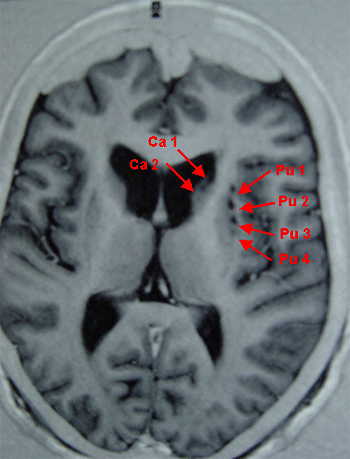

La maladie de Huntington

GreffeNeuronRMIR.gif